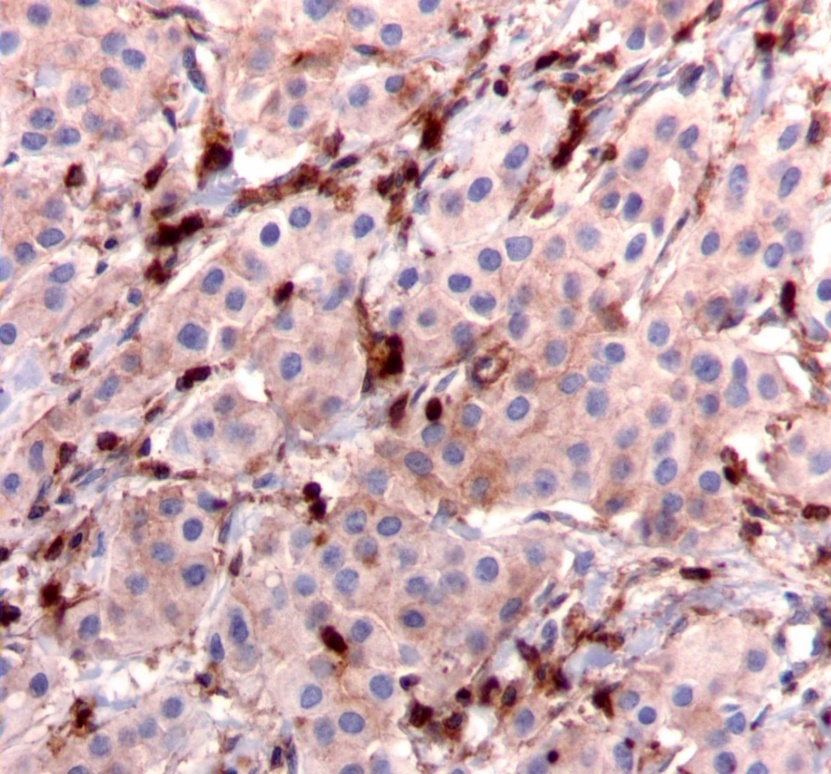

Figure 2.Diffuse cytoplasmic staining pattern for IRS-2. (IRS-2 immunohistochemical stain, 200x magnification)

We used the following histologic criteria for IRS-1 and IRS-2 staining patterns which are outlined in a previous study.13 For IRS-1, a nuclear pattern was defined as diffuse nuclear staining (Figure 1). IRS-2 staining patterns were defined using the following criteria: Diffuse cytoplasmic staining was defined as evenly distributed cytoplasmic reactivity (Figure 2); punctate cytoplasmic staining was defined as clearly demarcated puncta of staining within the cytoplasm (Figure 3); and membrane staining was defined as focal or diffuse membranous staining (Figure 4). Sections of normal pancreas and normal breast tissue were used for positive and negative controls. The pathologists assessing staining patterns were blinded to the tumor recurrence score and all other data at the time of assessment.